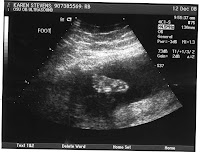

Fun with ultrasound pics, part 2

Fun with ultrasound pics, part 1